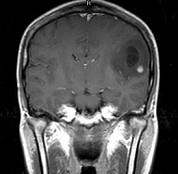

问题 女,33岁,三个月前有右上肢及右颜面部麻木,伴耳鸣及头昏,请根据所提供图像,选择最可能的诊断()

选项 A.脑脓肿 B.星形细胞瘤 C.脑结核 D.脑转移瘤 E.脑血吸虫病

答案 B